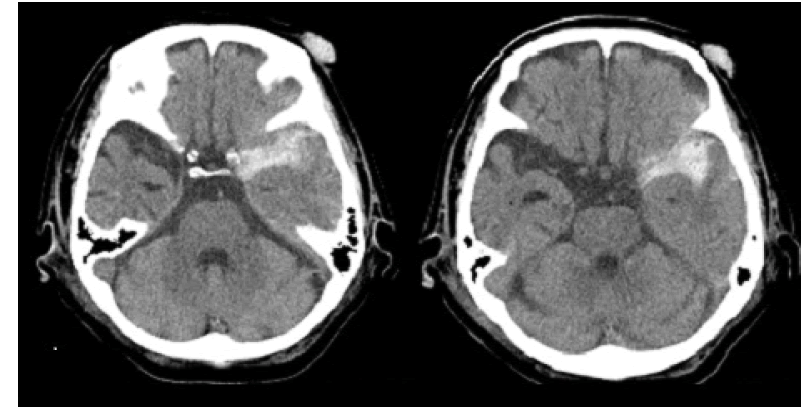

Figure 2: CT performed 4 days after head injury revealed massive subarachnoid hemorrhage in the left sylvian fissure; CT, computed tomography.